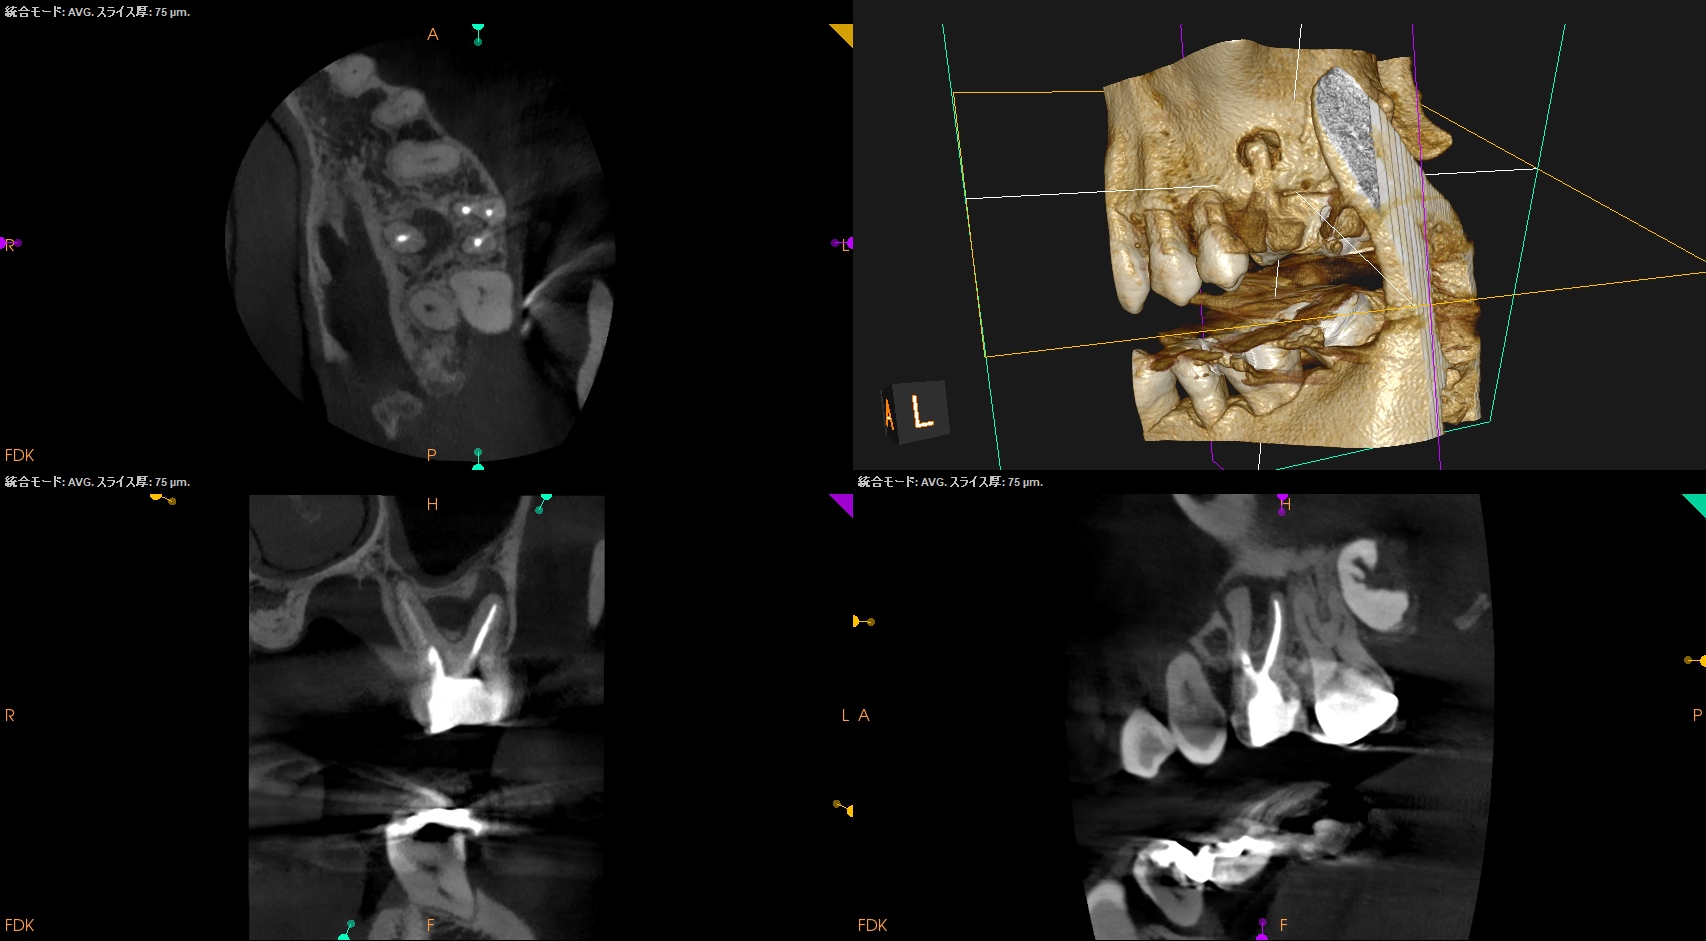

BC sealerを使用して根管充填した。

術後にPA, CBCTを撮影した。

MB1

MB2

DB

P

B

問題はないと思われる。

次回は1年後だ。